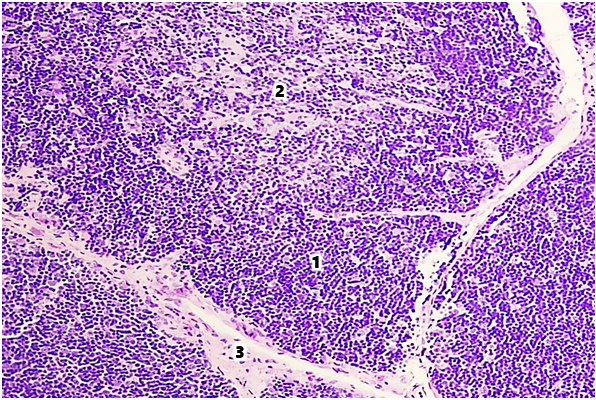

The thymus of laboratory animals of the control group consists of two interconnected lobes, located in the lower third of the sternum mesentery. The thickness of the capsule in the area of the thymus gate in healthy white outbred rats at 6 and 9 months of age was 5.82±0.32 and 5.97±0.38 μm, respectively. The diameter of the trabecula in the proximal part was 13.36±0.27 and 13.52±0.22 μm, respectively, and in the distal part 10.28±0.14 and 10.43±0.22 μm. The area of the thymus lobules was 64.27±0.12% and 52.27±0.48%, respectively, by age periods.The thickness of the capsule in the thymus gate area of white outbred rats in the group with modeled selenium deficiency increased by 6.87% at 6 months of age and 7.54% at 9 months of age compared to the indicators of white rats in the control group. It was established that the diameter of the proximal and distal parts of the trabecula increases by 1.05 and 1.06 times, respectively, in both age periods. The area of the thymus lobules decreased by 6.1% at 6 months of age, by 7.0% at 9 months of age, and amounted to 60.57±0.32% and 48.83±0.26%, respectively.In the histological preparations of the tissues of the thymus of healthy white outbred rats, the cortical and medullary layers are distinguished. The boundary between the cortical and medullary layers is not clearly defined. Fragments with parenchyma replaced by adipose tissue are identified. In 6- and 9-month-old laboratory animals of the control group, the area of the cortical layer of the thymus was 63.86±0.37% and 58.83±0.26%, respectively, and the area of the medullary layer was 28.52±0.38% and 32.92±0.42%, respectively (Fig. 1). | Figure 1. Thymus of a 9-month-old white rat in the control group. Stained with hematoxylin-eosin. Ok. 10 x vol. 10. 1st cortex, 2nd medulla, 3rd trabecula |